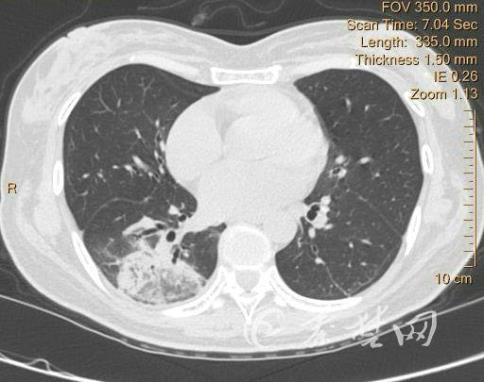

秦楚網(wǎng)訊 記者 張貞林 特約記者 李毅 報(bào)導(dǎo):傳染新式冠狀病毒后,患者的肺會(huì)成為什么樣?為什么有的人沒(méi)有任意病癥?有的人卻很嚴(yán)重,乃至危及生命?最近,國(guó)藥東風(fēng)總醫(yī)院借用3D技術(shù),順利打印出我市首個(gè)新冠肺炎患者肺部病灶模型,在臨床治愈中擁有絕對(duì)的引導(dǎo)功效。

11日,記者在國(guó)藥東風(fēng)總醫(yī)院CT室看見(jiàn),兩例新冠肺炎患者肺部病灶3D模型分外奪目。這是醫(yī)院按照新冠肺炎患者CT遠(yuǎn)古信息,借用3D打印技術(shù),以1:1的比率,做出的肺部3D模型。三維立體模型復(fù)原了患者的動(dòng)脈、靜脈、支氣管,能夠立體轉(zhuǎn)動(dòng)觀測(cè)。

據(jù)了解,常態(tài)人肺部CT展現(xiàn)的是彩色,但傳染后就會(huì)展現(xiàn)紅色,而依據(jù)病情的嚴(yán)重水平不同,肺部也會(huì)有不同樣的改變。

“黑色3D模型,相比CT照片更形象,能夠直觀的看見(jiàn)新冠肺炎病灶在肺部的1個(gè)體現(xiàn),綠色是新冠肺炎的病灶。”國(guó)藥東風(fēng)總醫(yī)院 CT室主任陳曉榮簡(jiǎn)介,與通常CT的平面圖片不同,三維立體模型更真正地復(fù)原了患者的肺動(dòng)脈、肺靜脈、支氣管,并且各構(gòu)造間的關(guān)聯(lián)和位子聯(lián)系,醫(yī)師針對(duì)病灶能夠立體轉(zhuǎn)動(dòng)觀測(cè),能更直觀、全面地了解患者的肺部病情進(jìn)展,制訂更精致化、個(gè)性化的后期治愈計(jì)劃,對(duì)臨床治愈有引導(dǎo)功效。